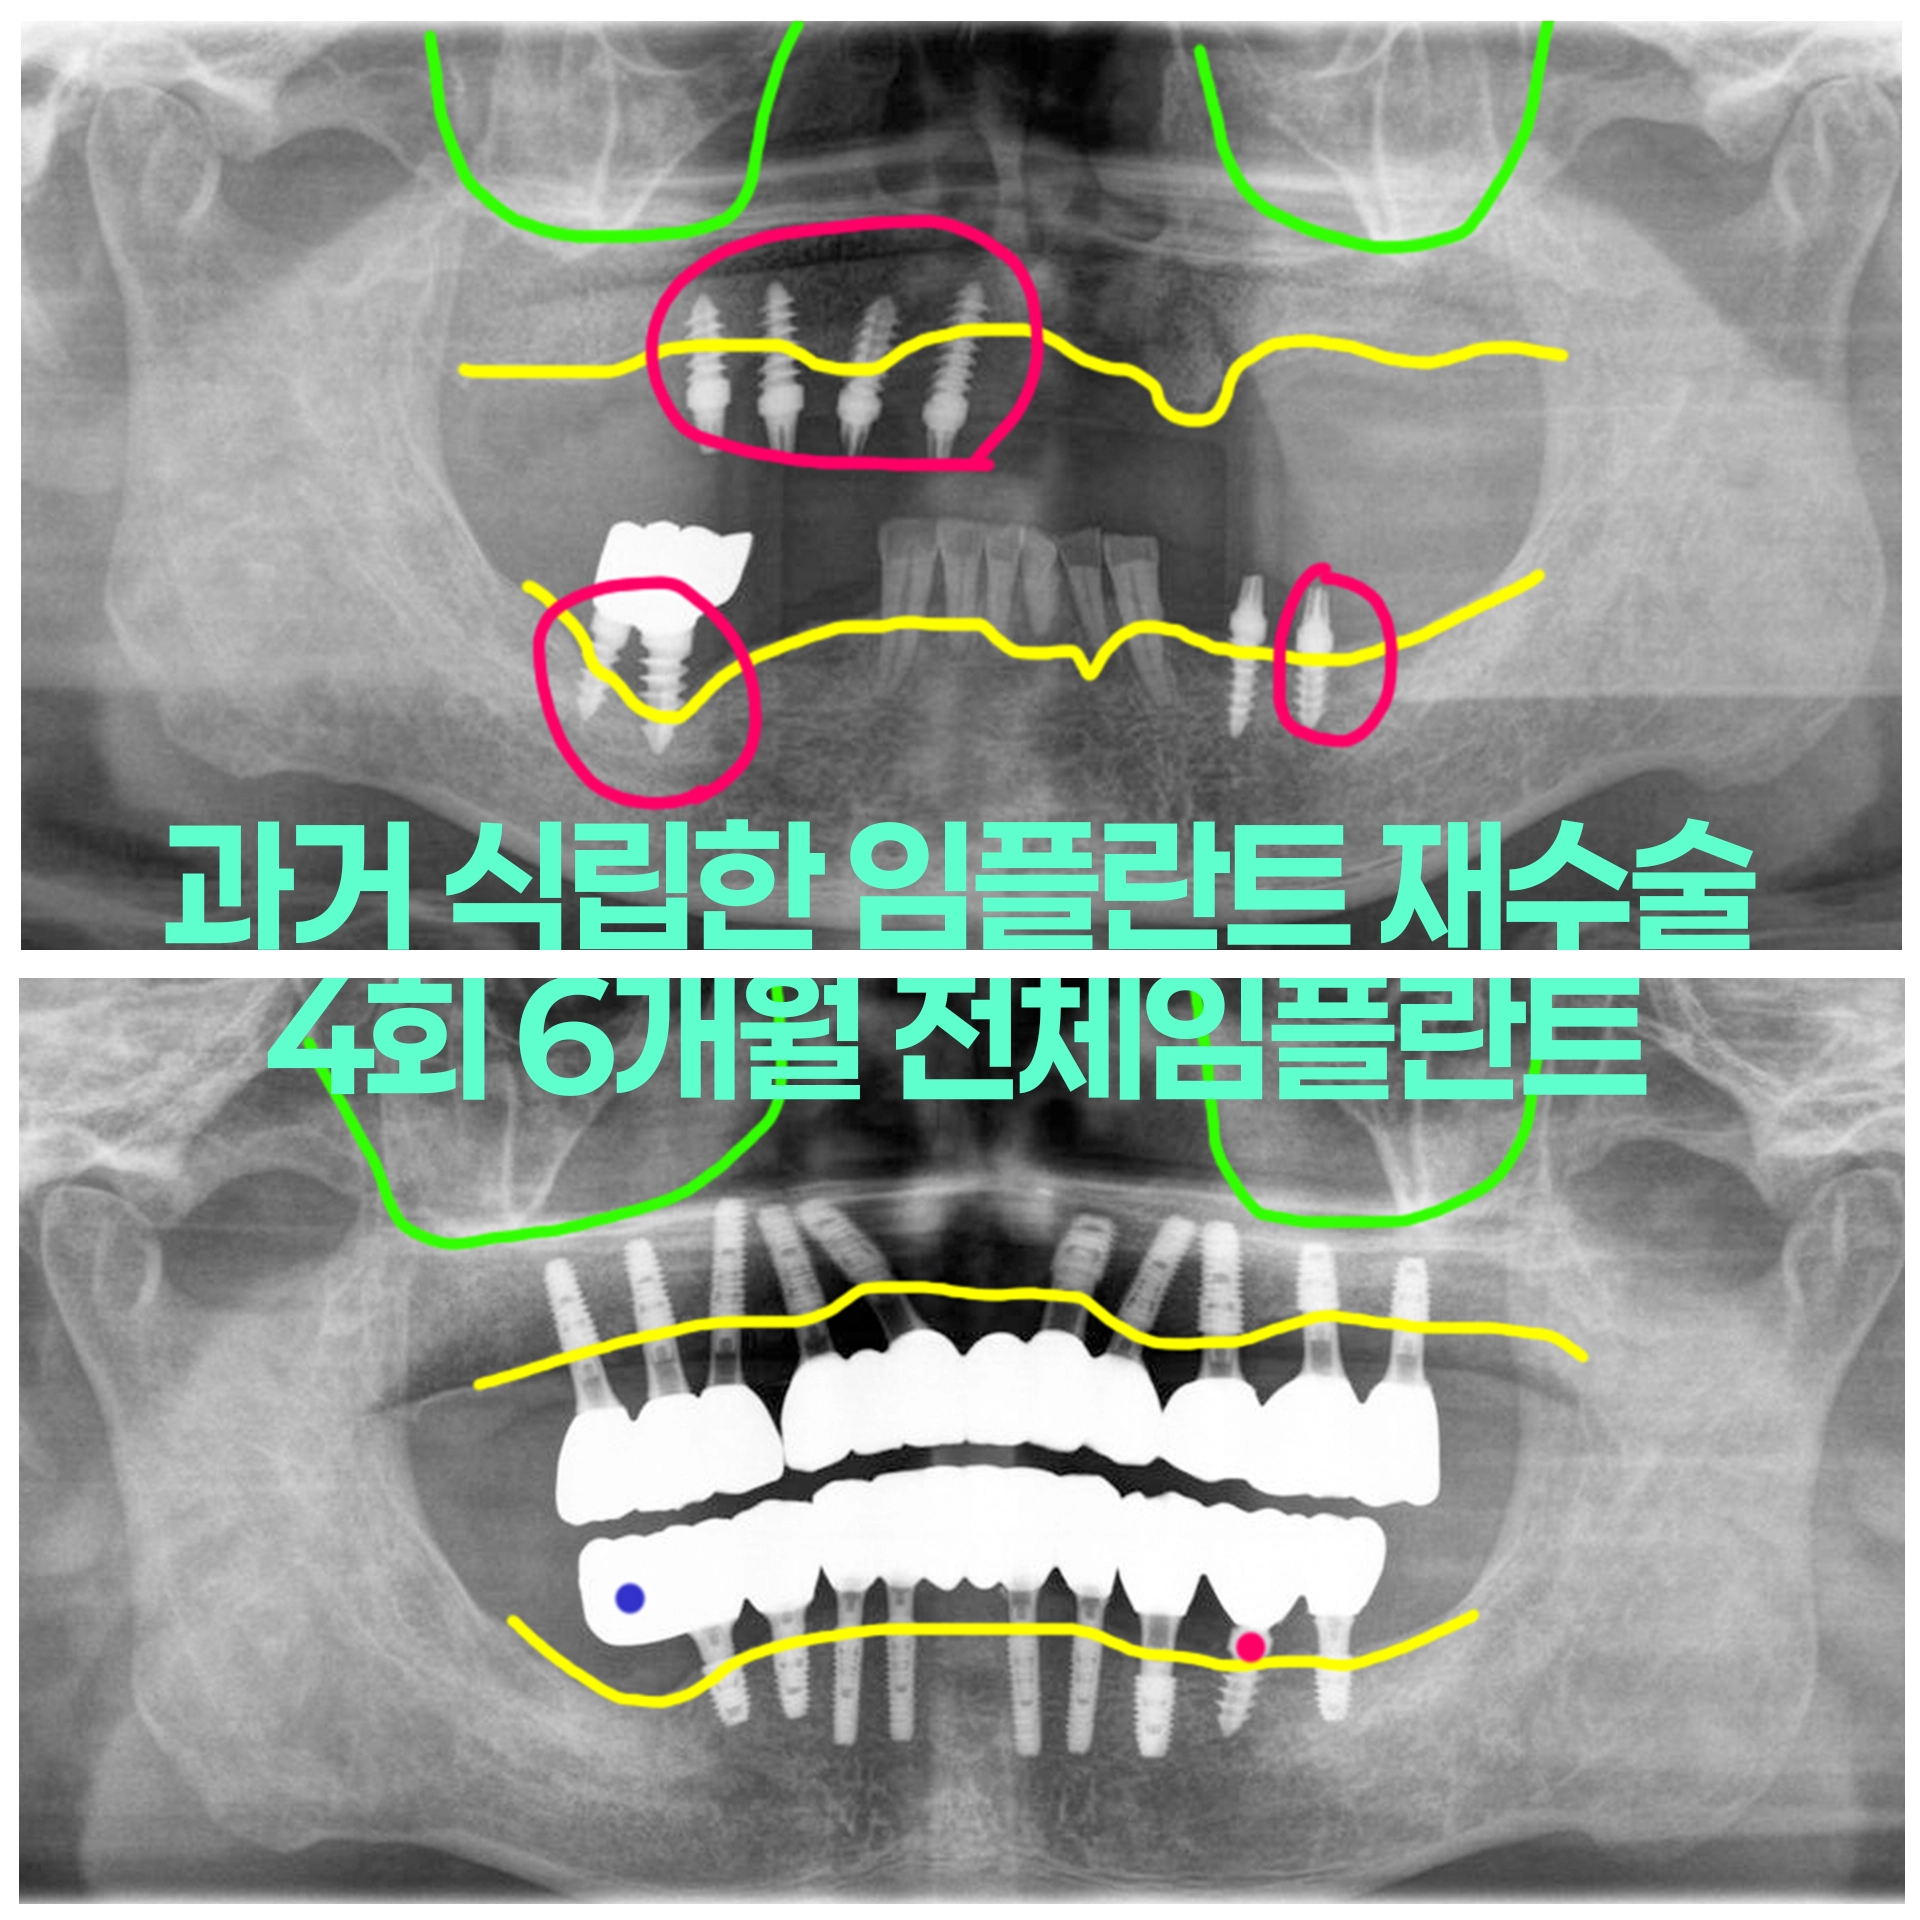

임플란트주위염으로 실패한 임플란트 제거와 많이 흔들리는 치아들 발치 후 전체임플란트